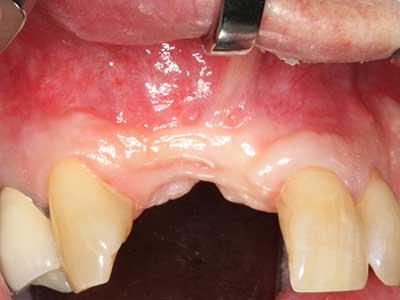

Fig. 13: Adequate irrigation with the 4-mm residual bone width is essential for this 52-year-old patient during the bone splitting.

Fig. 16: The intraoral conditions are also stable with embedding of the implants in keratinized gingiva.